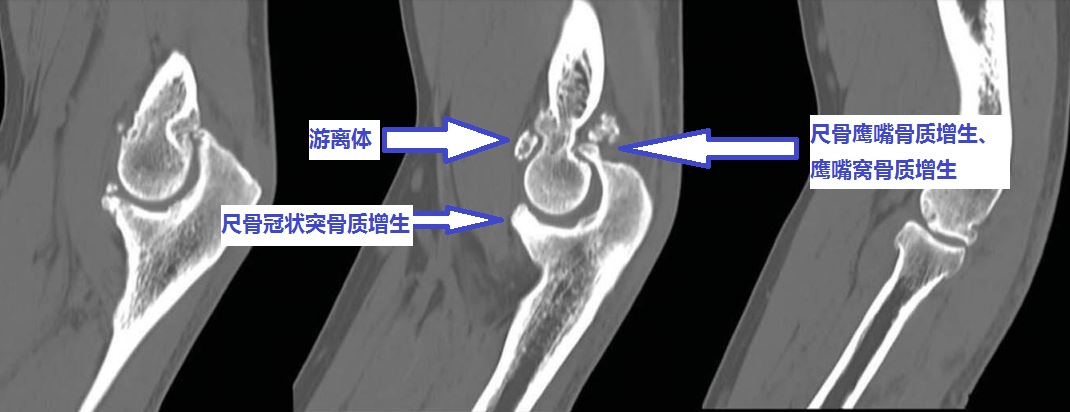

我们徐州1000万人口。其中有很多和您一样肘关节伸屈不行的患者。去年习*平近**主席两次到徐州视察进一步推进了我们徐州的快速发展。我们徐州发展过程中需要很多建筑工人。建筑工人师傅中有很多人来找我看肘关节问题。很多人都是由于肘关节骨性关节炎、肘关节游离体、肘关节骨质增生导致的肘关节僵硬。

伸不直往往是因为:1、尺骨鹰嘴骨质增生;2、肱骨远端后侧的尺骨鹰嘴窝骨质增生填塞;3、肘关节前侧的关节囊挛缩;4、肘关节内的游离体卡住了;等等。

屈不下来往往是因为:1、尺骨冠状突骨质增生;3、肱骨远端前面的尺骨冠状突窝骨质增生;4、肘关节后侧的关节囊挛缩;等等。